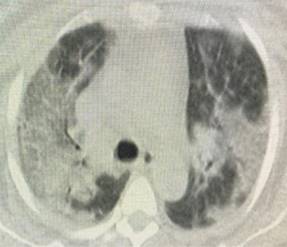

Presentamos una serie de casos de cuatro pacientes con SARS-CoV-2 con un compromiso importante de la oxigenación a pesar del uso de sistemas de alto flujo. En la Tabla 1 se describen grupos etarios, sexo, morbilidades, condiciones clínicas y escalas de severidad pronóstica de ingreso. Evolucionan tórpidamente frente al uso de cánula de alto flujo con índices de Rox por debajo de dos puntos en las primeras 12 horas.4 Se inicia ventilación mecánica no invasiva con progresión a falla respiratoria por aumento de la carga inspiratoria, por lo que requirieron protección de vía aérea. Se documenta un serio deterioro de la mecánica ventilatoria con sobredistención, aumento del trabajo respiratorio y caída de las distensibilidades; variables de monitoreo de la ventilación mecánica tomada en zona cero de flujo justo antes de cada inspiración. Adicionalmente evoluciona con importante deterioro de la ventilación minuto alveolar y de la oxigenación frente a la ventilación mecánica instaurada y a la posición prono, con poca tolerancia a la presión positiva direccionada por bucle presión volumen, meseta, fracción inspirada de oxígeno y curva presión tiempo.5-7 Con base en imágenes escanográficas que documentan infiltrados esmerilados, se describen cuatro campos pulmonares y zonas de condensación en las Figuras 1-4, además de compliance menor de 40 cm y requerimientos de PEEP entre 17 y 20 cm de agua, con el antecedente de volúmenes corregidos espiratorios durante la ventilación mecánica no invasiva entre 15 y 20 puntos se precisa SARS-CoV-2.8 Con base en la evolución descrita se decide instaurar protección pulmonar con 3 mL por kilogramo de peso más insuflación de gas traqueal con 5 L por min con el ánimo de ahorrar presión positiva de fin de espiración (PEEP por sus siglas en inglés positive end expiratory pressure), volumen tidal y velocidades de flujo. En la Tabla 2 se registra evolución gasimétrica antes y después de la estrategia. Se descartan coexistencias infecciosas de acuerdo al reporte de la microbiología. En los cuatro pacientes se documentaron defectos segmentarios de distribución vascular compatibles con enfermedad pulmonar tromboembólica. Evolucionan satisfactoriamente permitiendo desmontar estrategia de rescate con base en mecánica ventilatoria e índice de oxigenación,9 pudiendo implementar asa cerrada en asistencia proporcional con 40% de asistencia por flujo y volumen, PEEP de 10 cm y fracción inspirada de oxígeno de 50%. Se realizan monitoreos en asa cerrada que se muestran en la Tabla 3, documentándose trabajo respiratorio limítrofe, serio deterioro de las propiedades pulmonares mecánicas dinámicas y estáticas sin poder liberar de manera convencional, por lo que se programa para traqueostomía y traslado a cuidado crónico.